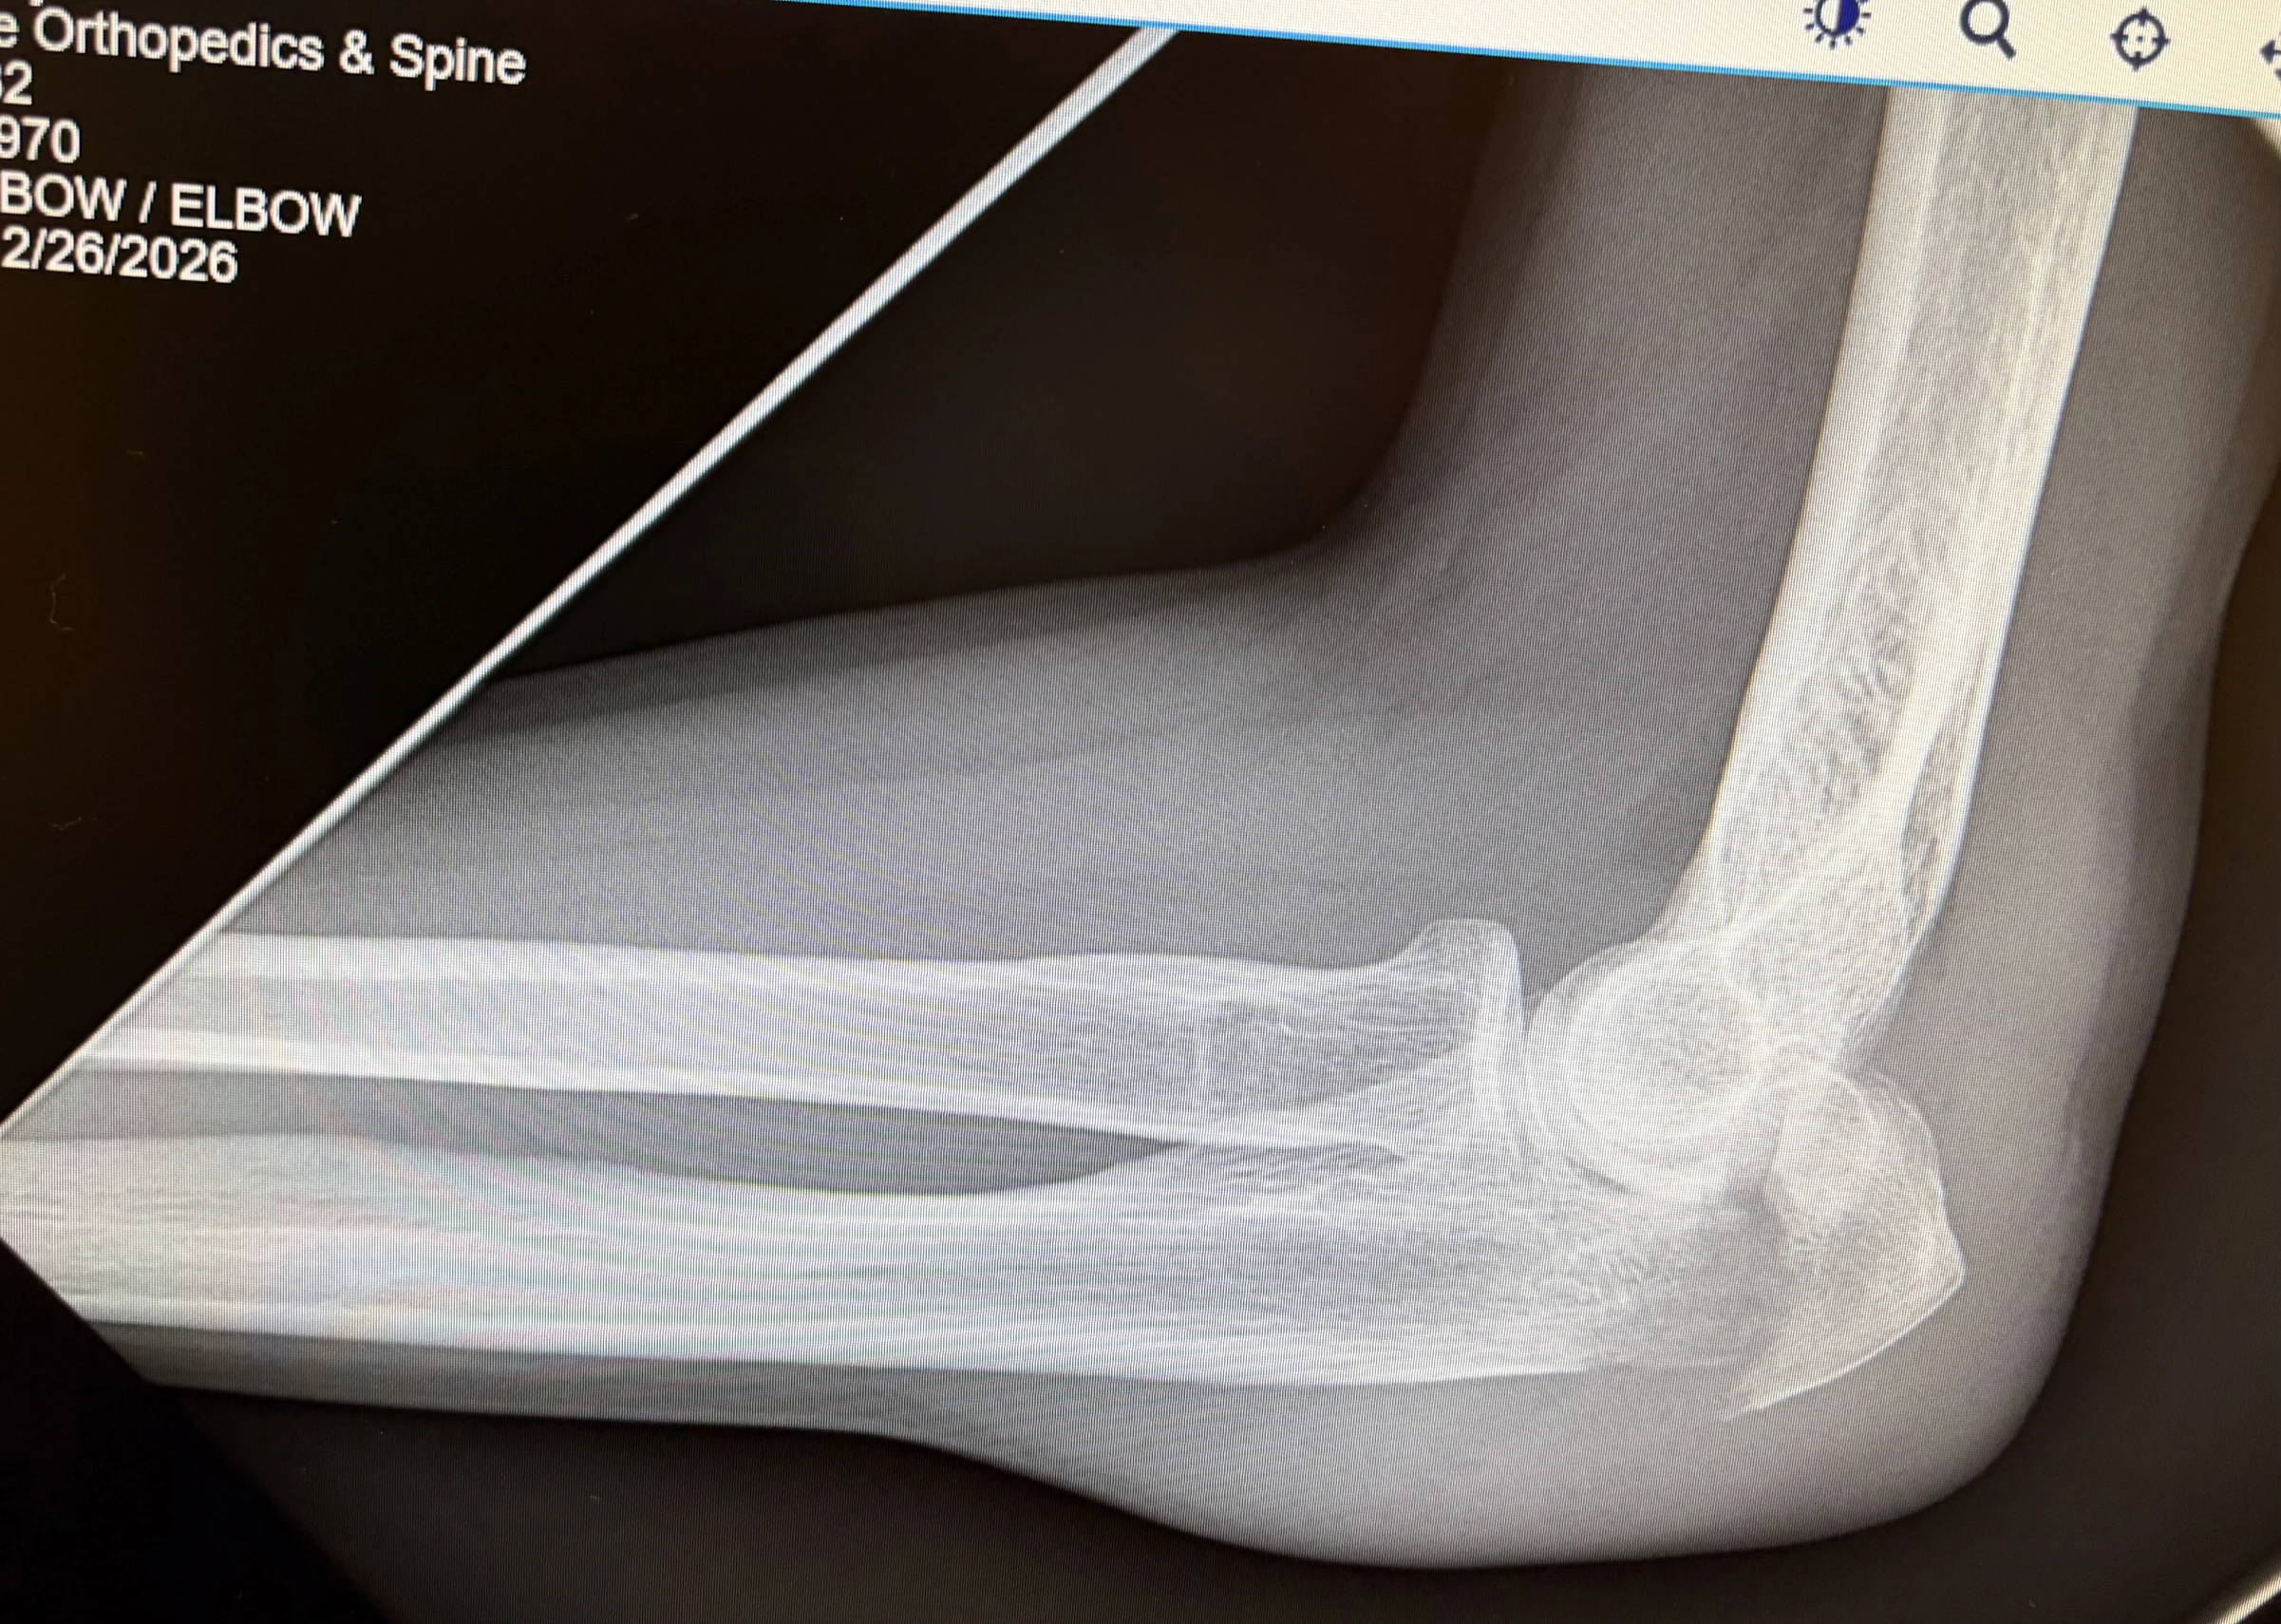

Bleah, so… I’m an idiot / can’t be trusted around fence posts. UNBELIEVABLY, only 2-1/2 years from breaking my right elbow in a bike crash, I break my left elbow, the same *damned way… 💥